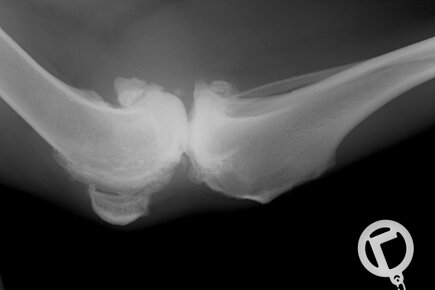

Der Knorpel, der die beteiligten Knochen überzieht, wird über die Zeit an den Stellen abgerieben, die durch die abnorme Flexibilität zu stark belastet sind. Der Körper versucht die entstehenden Defekte selbst zu heilen. Er bildet neue Knorpelmasse. Diese entspricht in Zusammensetzung und Form nicht dem ursprünglichen Knorpel. Es kommt zu Zubildungen, die dem Tier Schmerzen bereiten und zur Lahmheit führen. Auf dem Röntgenbild erkennt der Tierarzt kleine Knorpelauftreibungen, die an die jeweilige Stelle nicht hingehören. Oft ist das Gelenk etwas verdickt, da der Körper beim Versuch der Selbstheilung vermehrt Gelenkflüssigkeit produziert. Die Diagnose: Arthrose!

Es gibt Hunde- und Katzenrassen, die für gewisse Erbkrankheiten bekannt sind. Man denke an die Hüftgelenksdysplasie beim Schäferhund. Hier passen Oberschenkelkopf und Hüftgelenkspfanne nicht optimal zusammen. Der Kopf sitzt zu locker in der Pfanne. Diese mangelnde Kongruenz ist häufig genetisch bedingt. Durch die andauernde mechanische Belastung wird die dünne Knorpelschicht des Hüftgelenks abgenutzt. Es kommt zu den oben erwähnten Reparaturprozessen und Zubildungen. Große und gleichzeitig schwere Rassen sind besonders häufig betroffen. Zu den bekanntesten Arthrosen gehören die Coxarthrose (Hüftgelenksdysplasie), Gonarthrose (Kniegelenksarthrose) und die Spondylose (Arthrose der kleinen Gelenke der Wirbelsäule).